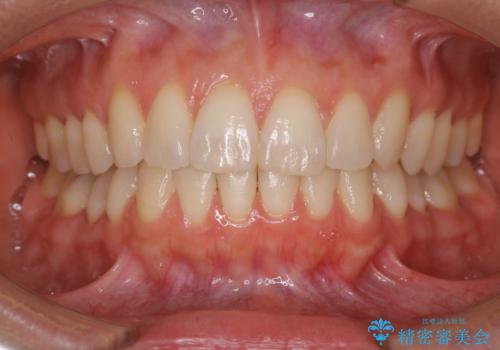

再矯正、後戻りを治したい、マウスピース矯正

途中で終わってしまったワイヤー治療もインビザラインで

抜歯矯正の後戻りが気になる インビザライン・ライトによる矯正治療